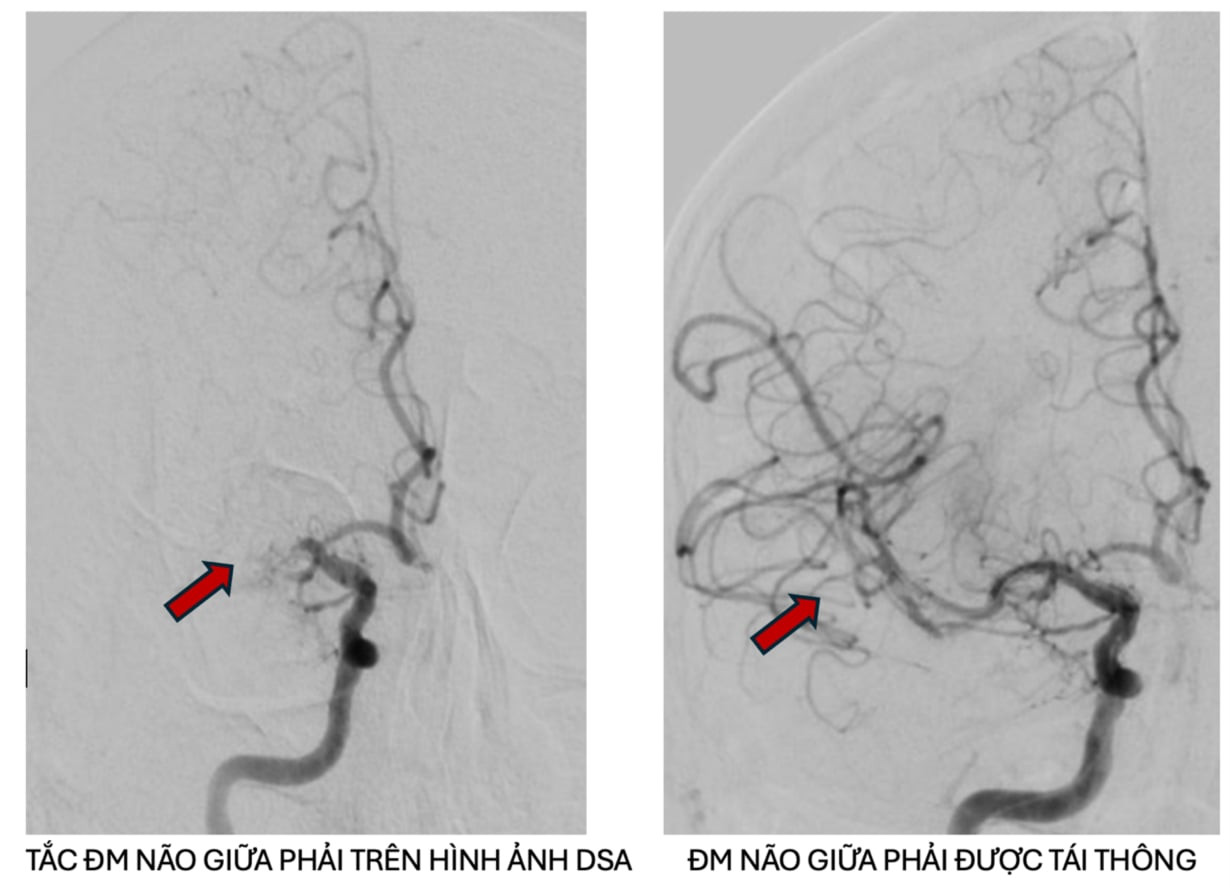

Người bệnh ngay lập tức được thực hiện chụp MRI tưới máu não kết hợp với phần mềm trí tuệ nhân tạo RAPID AI để đánh giá vùng mô não bị tổn thương. Kết quả cho thấy bệnh nhân bị tắc động mạch não giữa phải trên nền hẹp nặng do xơ vữa động mạch, có chỉ định can thiệp mạch não lấy huyết khối. Người bệnh được chuyển ngay đến Đơn vị can thiệp mạch máu thần kinh tiến hành lấy huyết khối và nong vị trí hẹp mạch máu, kết quả động mạch được tái thông tốt sau can thiệp.